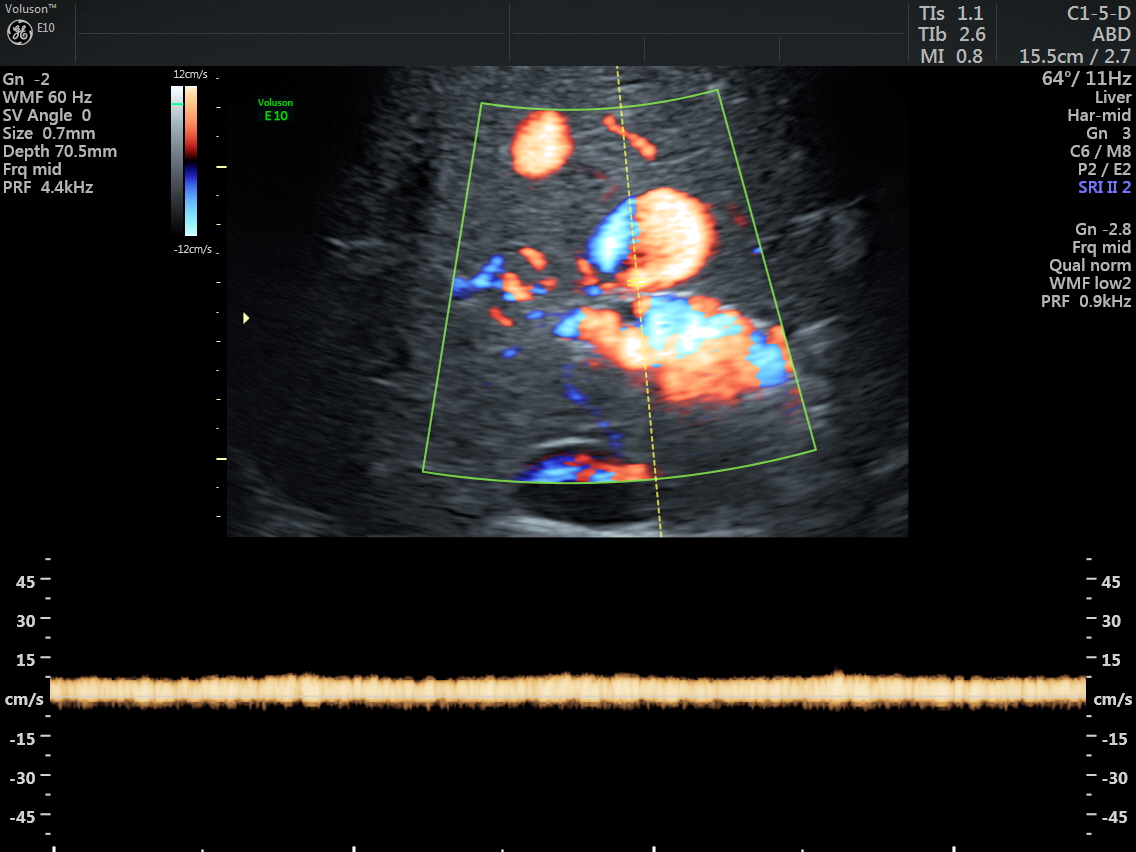

The venous flow is established by power doppler in the following pictures.